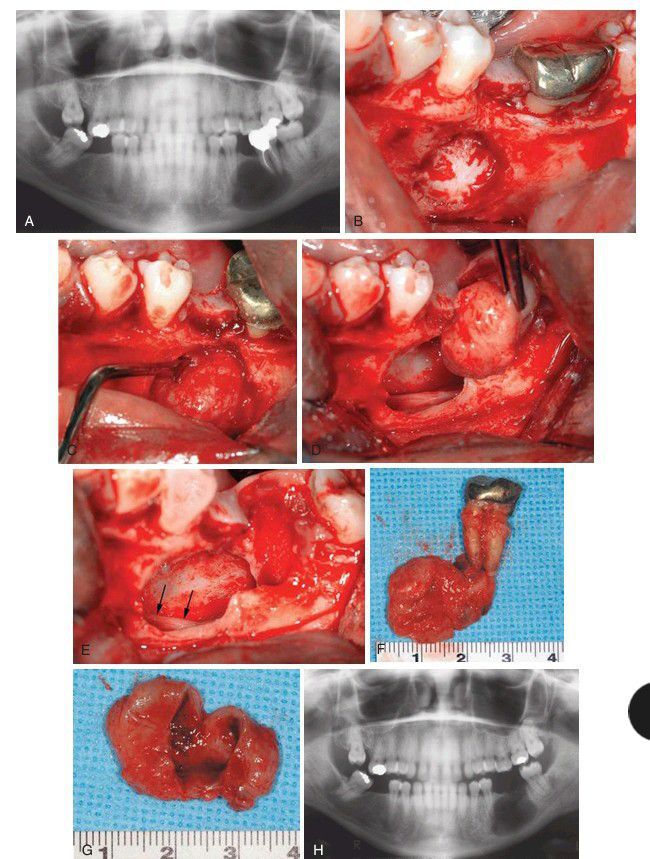

A clinical case of apical cystectomy performed at time of tooth extraction. (A) Pretreatment panoramic radiograph showing large radiolucent lesion at the apices of teeth No. 18 and 20. (B) Incision designed to ensure that the incisions are located over intact bone after cystectomy. (C) Appearance of the lesion after the buccal flap is elevated. Note that the lesion has eroded the bone. (D) Curette used to elevate the lesion from the bony walls. (E) Cyst being removed. (F) Note the inferior alveolar neurovascular bundle passing along the inferior aspect of the bony cavity. (G) Surgical specimen. (H) When opened, the specimen appeared to be cystic. The patient should be monitored with periodic radiographs to ensure bone fill and no recurrence of the lesion.